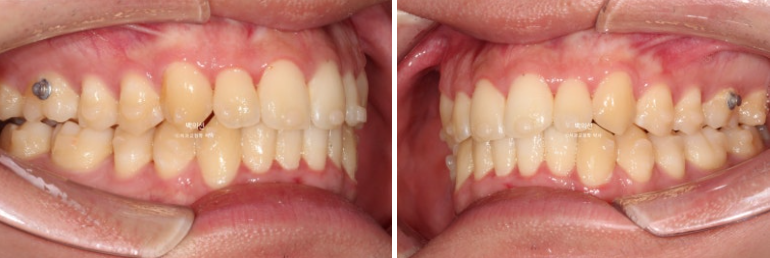

25.02~25.08

아래 앞니의 배열 개선이 드라마틱 하네요. 안으로 쓰러진 작은어금니들 배열도 좋습니다.

교정 후 아래 앞니 잇몸 라인 높낮이가 자연스럽게 맞아진 것이 보입니다.

치아 높이가 교정으로 맞아지면 잇몸라인은 자연스럽게 맞아집니다.